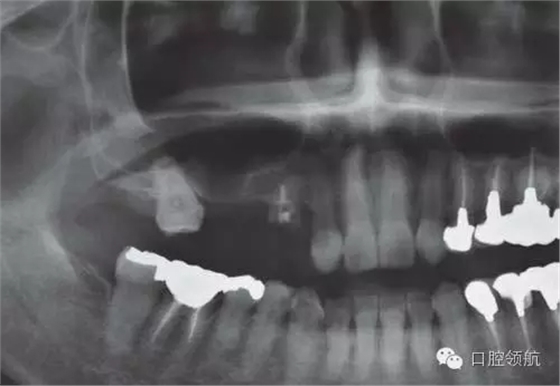

(左上第四顆牙)拔牙后即刻種植,(左上第五、六顆牙)位置用β-TCP做上頜竇內提升同期植入種植體的病例(圖1)。

圖1 術前的曲面斷層影像

這個病例,上頜竇底骨量不足,利用內提升的方法同期植入。

為了在不足的骨量中獲得良好的初期穩(wěn)定性,種植體沒有埋入過深,所以造成軟組織的不足,雖進行減張切開縫合,但術后仍出現牙齦裂開(圖2~圖5)。